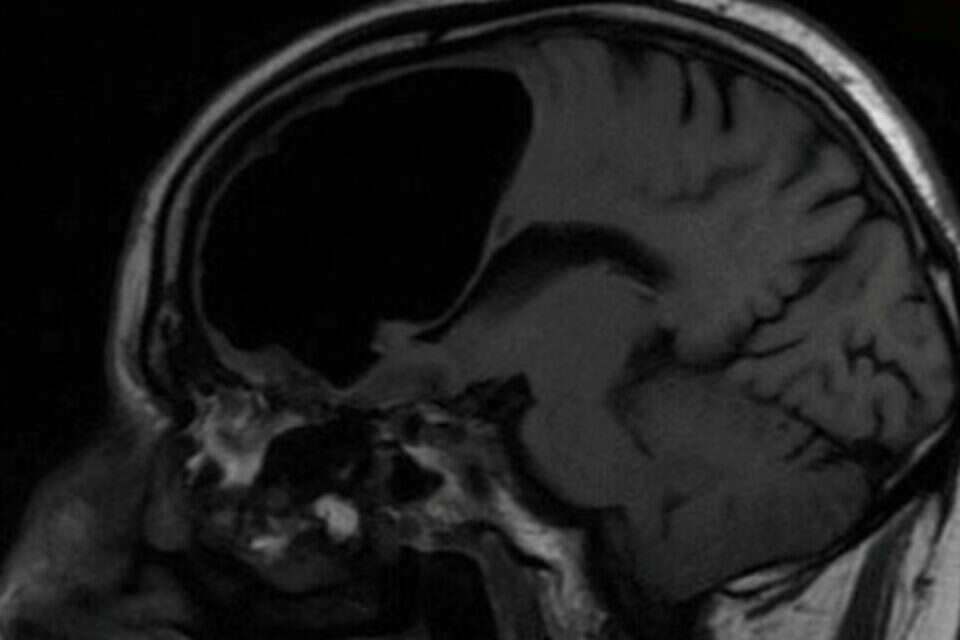

צילום: Getty Images // כיס האוויר בראשו של החולה // צילום: טוויטר, BMJCaseReports

כיס האוויר בראשו של החולה // צילום: טוויטר, BMJCaseReports

הסריקות שביצעו בראשו של החולה גילו ממצא יוצא דופן – כיס אוויר בגודל של 3.5 אינץ' (8 ס"מ). התופעה, המכונה "פנאומטוקל", מתרחשת באונה המצחית, האחראית בין היתר על ביצוען של תנועות גוף.

בסריקת ה-MRI של הפציינט נמצא גם גידול שפיר קטן שגורם לאוויר להיכנס אל תוך מוחו. "זה כמו בבקבוק קולה – לפעמים יש שסתום חד כיווני שמאפשר לאוויר להיכנס ולא לצאת", הסביר ד"ר אלאן כהן, רופא נוירוכירוגי שלא היה מעורב באירוע המדובר.